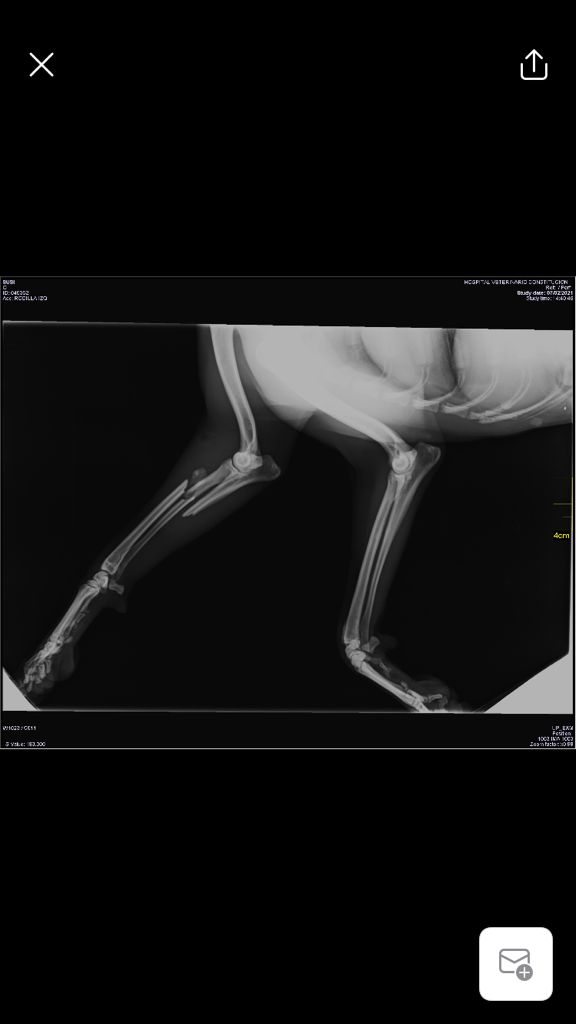

Sushy apareció atropellada en la carretera, de alli la llevaron a la perrera, donde querian sacrificarla, por suerte unas personas la sacaron y nos pidieron ayuda para ella, despues de traerla desde valencia ingreso en un hospital veterinario donde la operaron 3 veces, se paso varias semanas ingresada y cuando por fin salio a una casa de acogida se dio cuenta de que engordo en 3 dias y se le inflamaron las mamas.